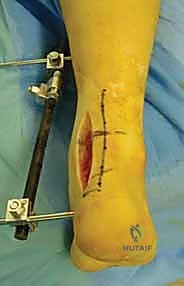

المرحلة الثانية: النهج الجراحي (الشقوق الجراحية)

نظراً لتعقيد عظم الكاحل، غالباً ما يتطلب الأمر شقين جراحيين (Dual Approaches) للوصول إلى العظم من زوايا مختلفة دون تدمير الأنسجة السليمة:

* النهج الأمامي الإنسي (Anteromedial Approach): شق يتم إجراؤه على الجانب الداخلي للكاحل، بين وتر العضلة الظنبوبية الأمامية والكعب الإنسي. يتيح هذا الشق رؤية ممتازة لعنق الكاحل والجانب الداخلي لجسم العظم. في بعض الحالات المعقدة، قد يضطر الدكتور هطيف لإجراء "قطع عظمي للكعب الإنسي" (Medial Malleolar Osteotomy) للوصول إلى عمق المفصل، ثم إعادة تثبيته لاحقاً.

* النهج الأمامي الجانبي (Anterolateral Approach): شق يتم إجراؤه على الجانب الخارجي، يتيح رؤية النتوء الجانبي، المفصل تحت الكاحلي، والجانب الخارجي للعنق والجسم.